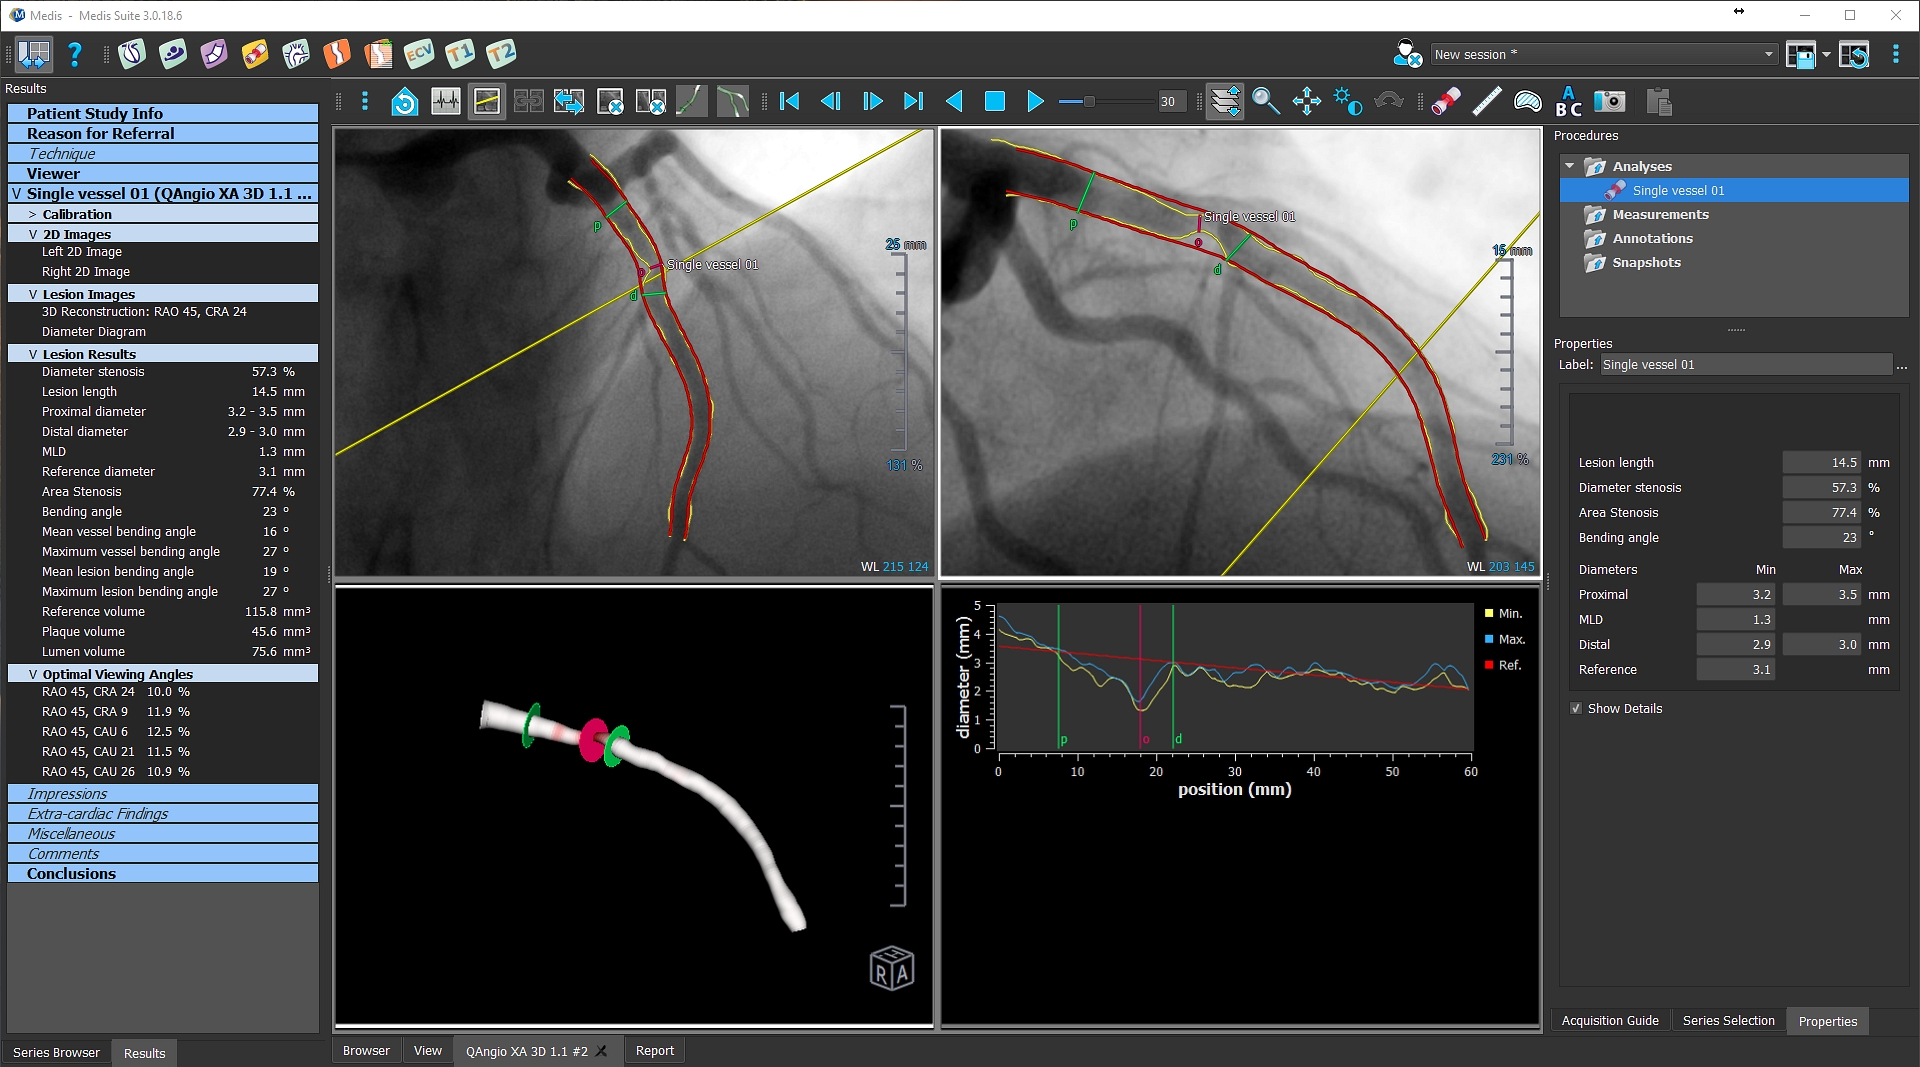

3D QCA analysis

Can be applied to monoplane and biplane acquisitions • Accurate offset correction between the projections • Calibration based on Isocenter data • Efficient Acquisition Guide suggesting optimal viewing angles for second acquisition • Automatic 2D and 3D contour detection and quantification • Calculation of optimal viewing angles for subsequent treatment • Calculation of lesion foreshortening • Support for ECG visualization • Easy wizard for intuitive guided workflows